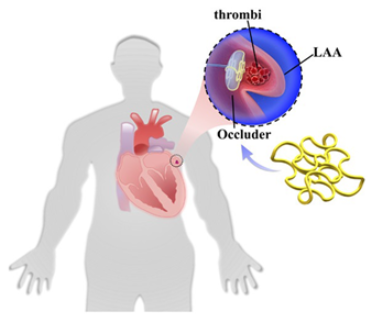

1.1. Left Atrial Appendage and Stroke Prevention in Patients Experiencing Atrial Fibrillation

2. Current Solutions for LAA Closure